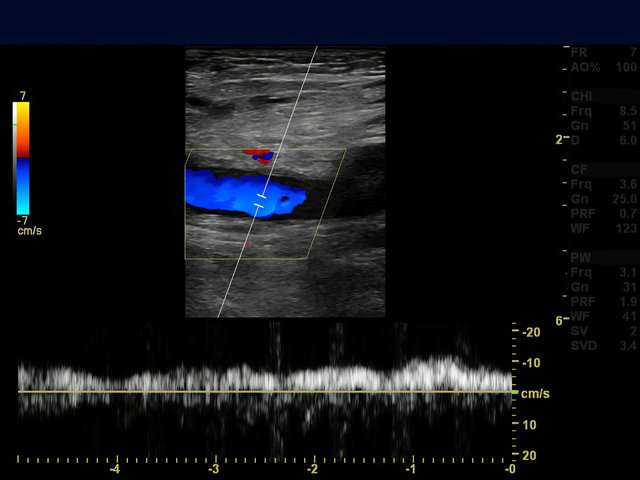

경동맥 초음파는 초음파 장비를 사용하여 목 부위에 위치한 경동맥의 상태를 확인하는 검사입니다. 경동맥은 심장에서 뇌로 혈액을 공급하는 중요한 혈관으로, 이 혈관이 건강하지 않으면 뇌졸중과 같은 심각한 질환으로 이어질 수 있습니다. 경동맥 초음파 검사는 비침습적이며 방사선을 사용하지 않아 안전하게 시행할 수 있는 장점이 있습니다.

- 뇌졸중 위험: 혈류가 원활하지 않으면 뇌로 가는 혈액 공급이 차단될 위험이 있습니다. 초음파를 통해 뇌졸중 발생 가능성을 조기에 파악할 수 있습니다.

- 플라크(혈전) 확인: 혈관 내 플라크를 확인하여 혈전 발생 여부를 미리 파악하고 예방할 수 있습니다.